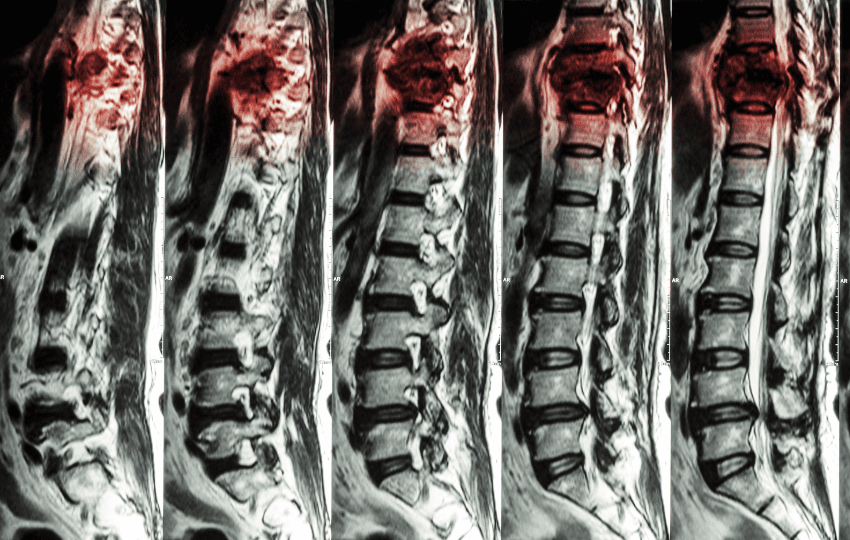

Ressonância magnética (RMN) é o exame de escolha para o diagnóstico da síndrome de compressão medular. Deve abranger toda a coluna (cervical, torácica e lombossacral), sem e com contraste. Permite localizar a compressão, avaliar extensão epidural e paravertebral e identificar lesões intramedulares ou leptomeníngeas.

É importante avaliar outros segmentos da coluna, pois múltiplas lesões epidurais coexistem em cerca de um terço dos pacientes.

Tomografia computadorizada com mielografia é alternativa quando RMN é contraindicada (dispositivos cardíacos, corpo estranho metálico).